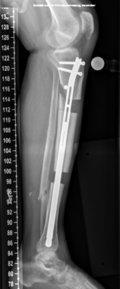

Von der Fraktur über die Pseudarthrose zum Segmenttransport

Vorgeschichte: Herr M. zog sich vor drei Jahren im Rahmen eines BG-lich versicherten Motorradunfalls eine I°ig offene mehrfragmentäre Tibiaquerfraktur mit 2-Etagen-Fraktur der Fibula links sowie eine OSG-Luxationsfraktur rechts zu.

Die initiale Versorgung erfolgte in einer Klinik der Maximalversorgung mit Fixateur extern Anlage und Transfixation des Sprunggelenks. Im Verlauf erfolgte der Verfahrenswechsel auf einen Tibia-Nagel links und Fibulaplatte mit Zuggurtung des Innenknöchels rechts.

Bei Fistel über der Unterschenkelfraktur links erfolgte etwa 9 Monate nach dem Unfall die Fistelexzision, mehrfaches Markraummüberbohren mit Jet-Lavage sowie die erneute Wundunterdruck-Therapie. Bei Keimnegativität erfolgte eine erneute Marknagelosteosynthese mit Schwenklappenplastik und Spalthaut zum Verschluss des Defekts.

Rekonstruktion: Bei Infektverlauf mit Nachweis von Staphylococcus aureus und Staphylococcus epidermidis sowie histologischem Nachweis einer chronischen Osteomyelitis an der linken Tibia erfolgte 1,5 Jahre nach dem Unfall die Infektsanierung mit Segmentresektion und anschließend der Segmenttransport mittels Precice-Bone-Transport-Nail.

Nach etwa 2 Monaten konnte das Kompressionsdocking erfolgen. Bei weitgehender Konsolidierung über ein Jahr nach der Implantation erfolgte die Metallentfernung des einliegenden Segmenttransport-Nagels sowie die Anpassung eines Braces zur weiteren Ausbehandlung.

Resümee: Erst durch die konsequente Segementresektion konnte der Infekt eradiziert werden. Durch die Therapie mit dem noch relativ neuen Verfahren des Segmenttransportnagels konnte dem Patienten die zwar ebenfalls meist erfolgreiche, jedoch deutlich belastendere Therapie mit einem Ringfixateur erspart werden.